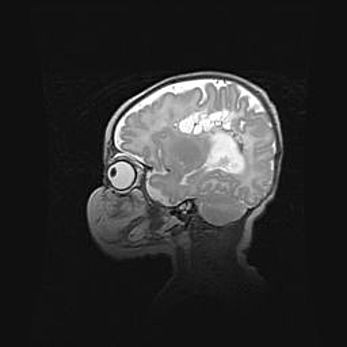

Неполная лизэнцефалия (пахигирия). Открытая гидроцефалия.

Возраст: 17 дней

Вес: 3110 г

Пол: мужской

Окружность головы: 33,5 см

Срок гестации: 35-36 недель

Лизэнцефалия—недоразвитие корковой пластинки и мозговых извилин в результате нарушения миграции нейронов коры. Поверхность мозговых полушарий гладкая. Микроскопически выявляется отсутствие нормальных слоев коры и скопление групп нейронов в подкорковом белом веществе.

Пахигирия—уменьшение числа вторичных извилин. В пораженном полушарии нервные клетки образуют толстый недифференцированный слой с неправильно расположенными нервными волокнами и группами гетеротопных клеток. Нервные клетки незрелые. Белое вещество истончено. При этом нередко аномально развит корково-спинномозговой путь.